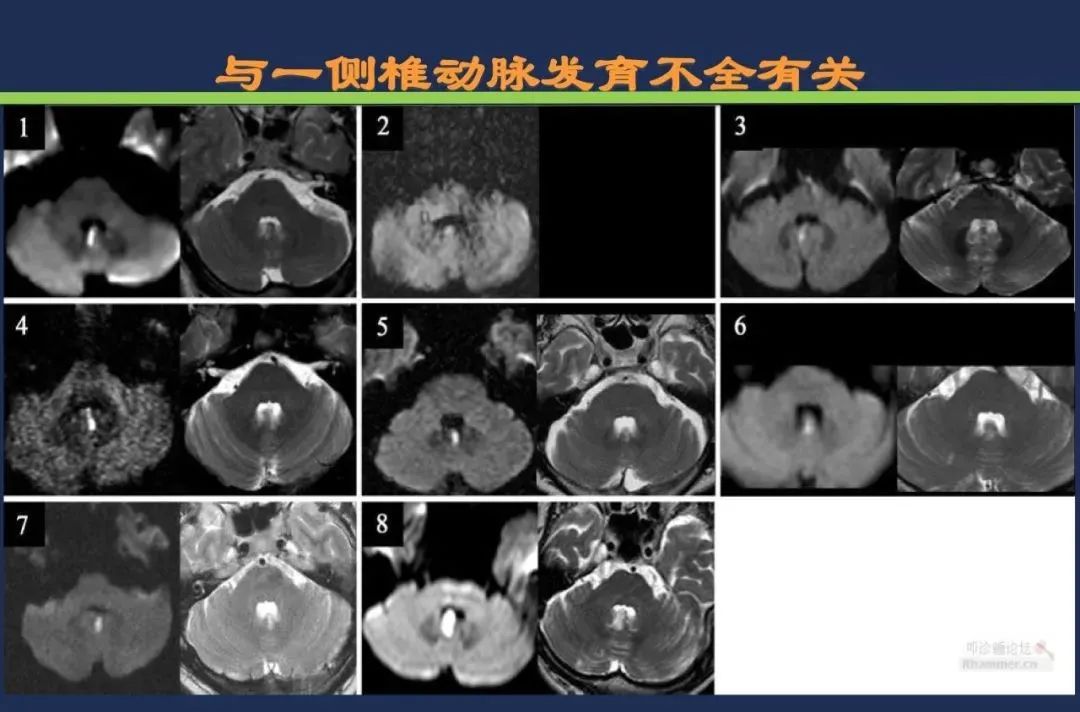

椎基底动脉梗死大脑后动脉丘脑穿通动脉-Percheron动脉